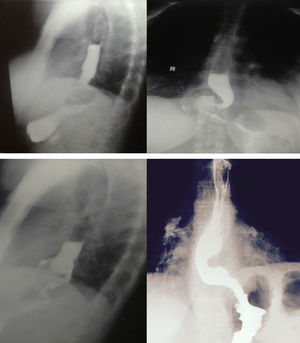

Clasificación de Horgan para la funduplicatura fallida30 (fig. 4):

- –

Tipo I: UEG herniada a través del hiato, con funduplicatura (IA) o sin la funduplicatura (IB).

Tipo II: involucra un componente paraesofágico resultado de una plicatura redundante.

Tipo III: malformación (defecto en la posición o construcción) de la plicatura.

Figura 4.Tipos de funduplicatura fallida (clasificación de Horgan). A) Tipo Ia: hernia sin herniación de la funduplicatura. B) Tipo Ib: con herniación de la funduplicatura. C) Con desplazamiento paraesofágico. D) Defecto en la formación de la plicatura.

Tomado de Horgan y Pellegrini30.